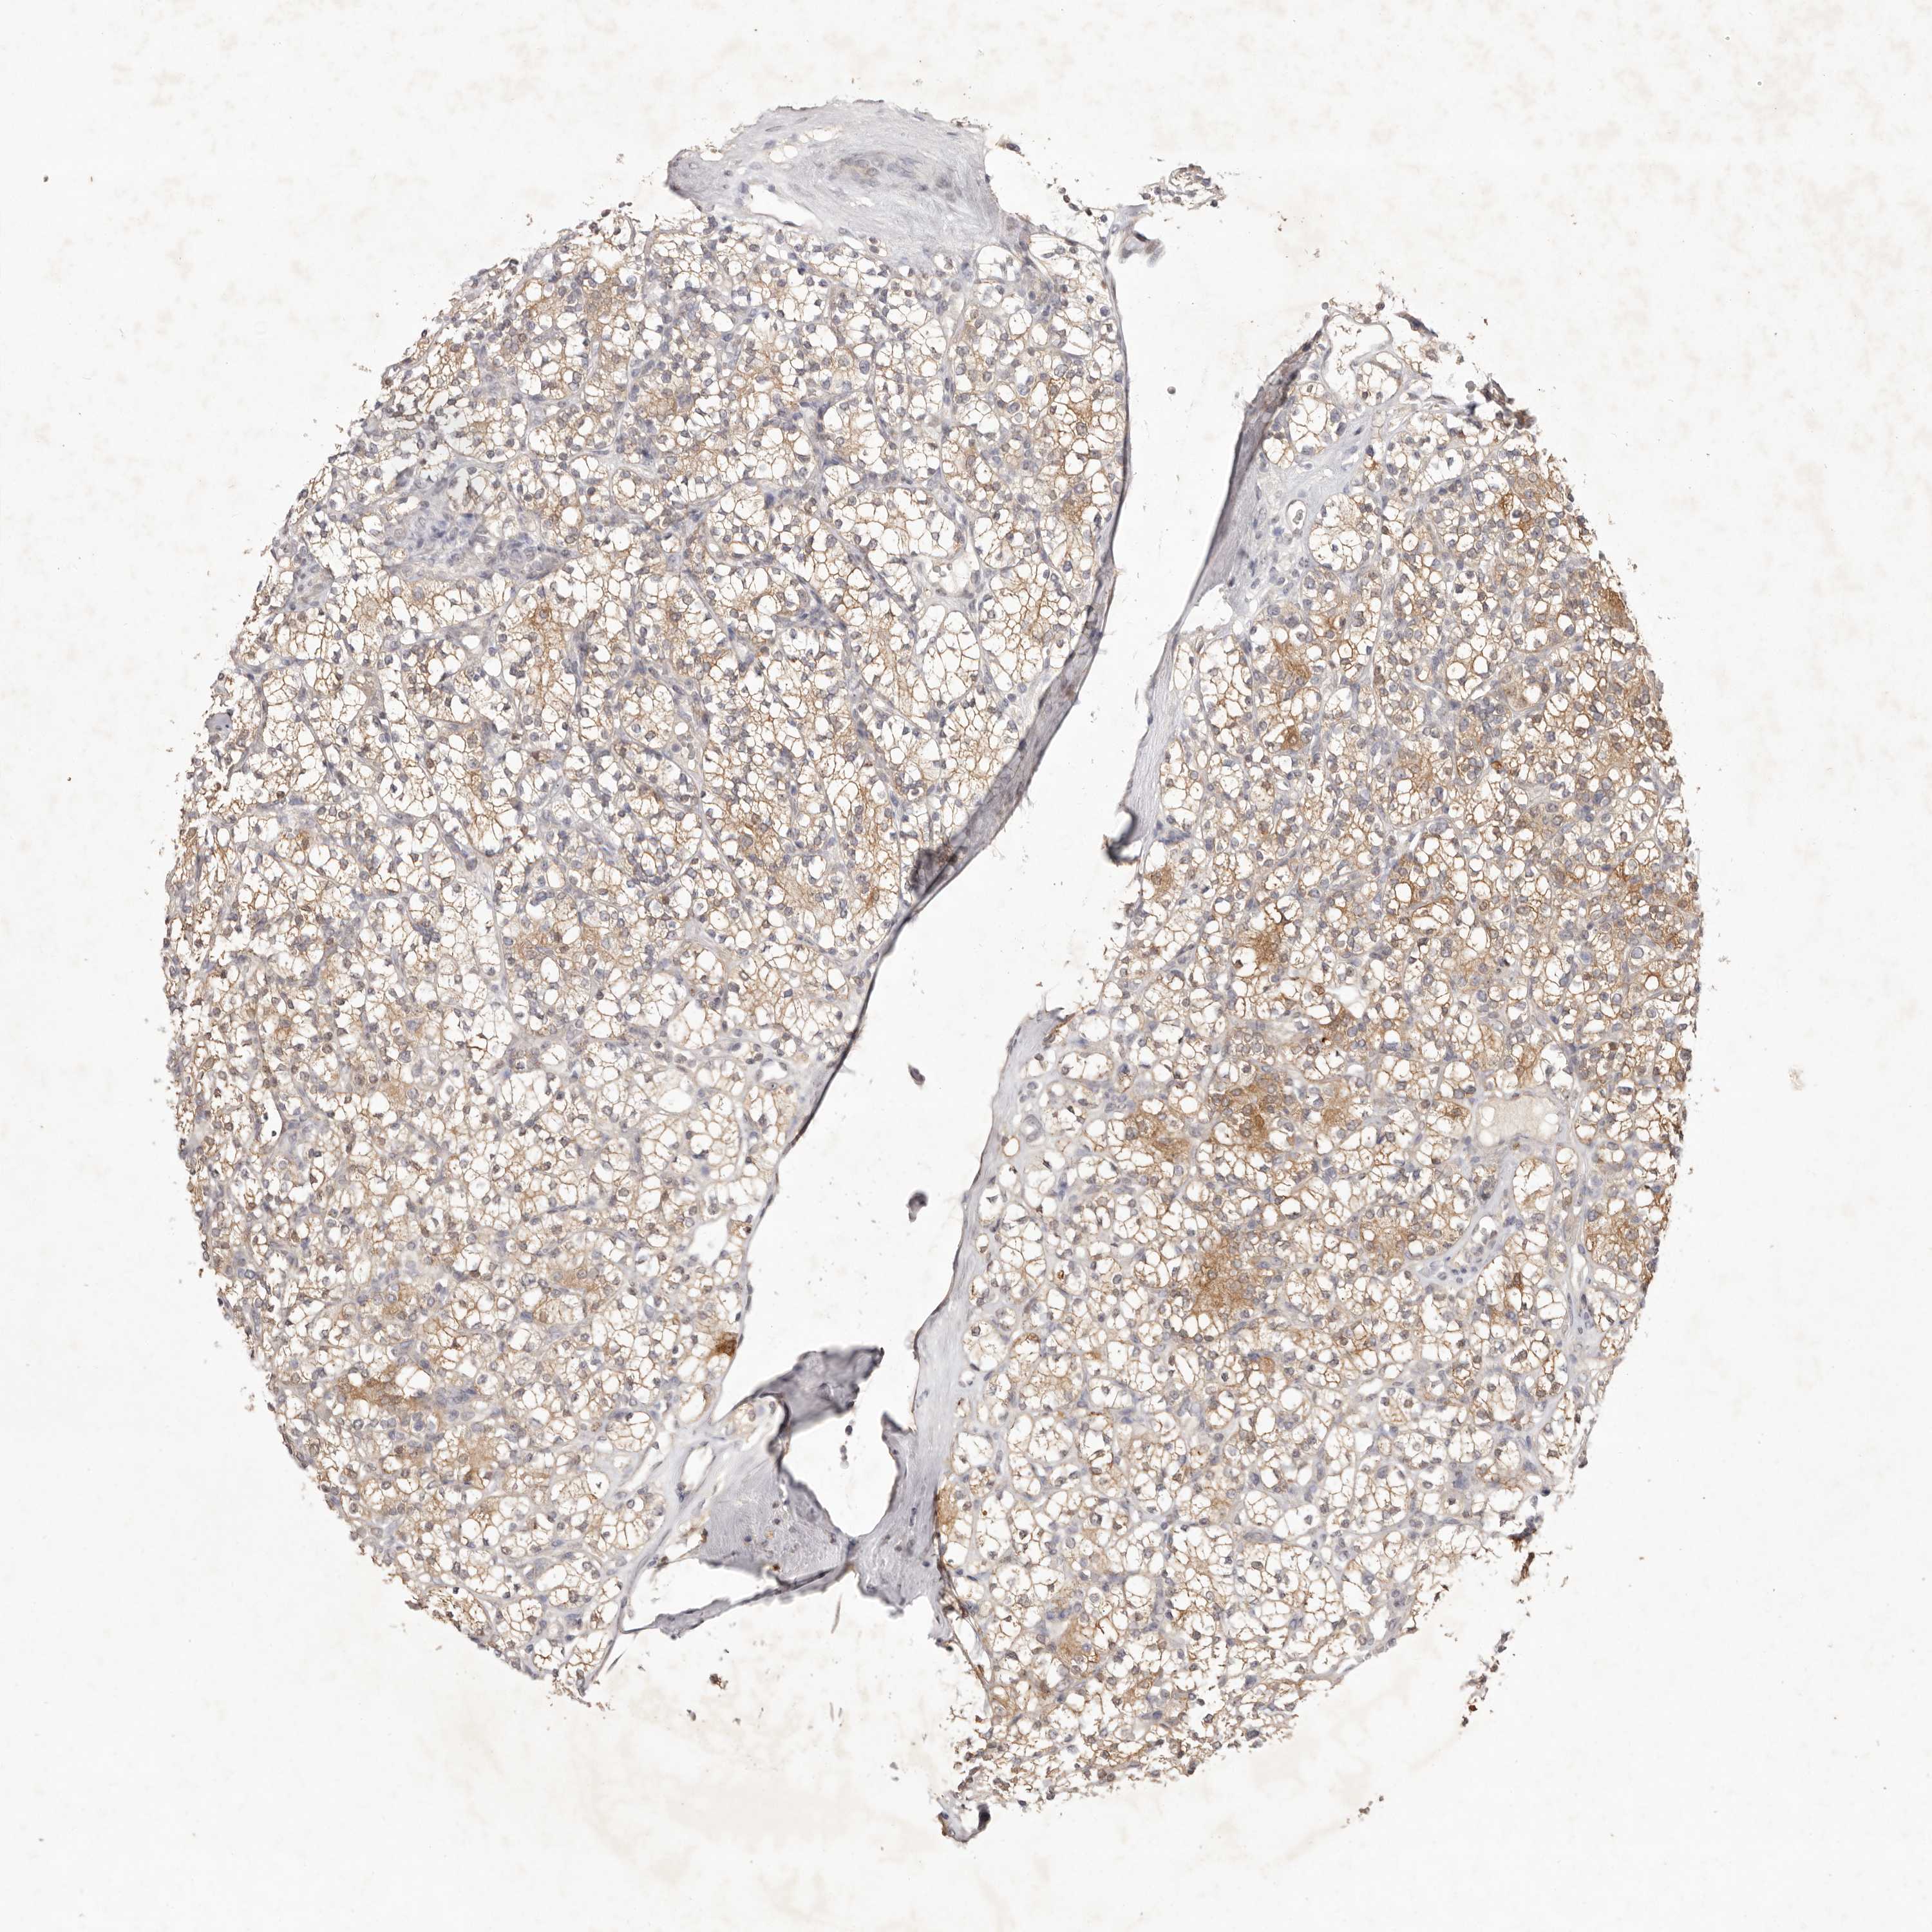

CANCER RENAL CANCER Show tissue menu

KICH TCGA KIRC TCGA KIRC VALIDATION KIRP TCGA PROTEIN RCC CPTAC PROTEIN EXPRESSION